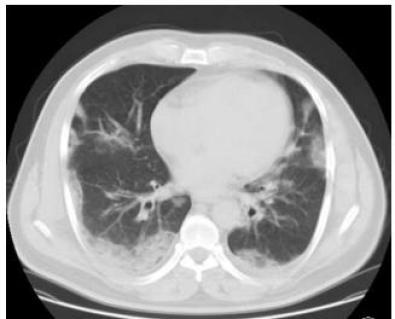

▎流感

流感,特别是甲流,也会表现为胸膜下为主的磨玻璃,但是出现的几率小于新冠肺炎。

下面的患者,就是甲流病毒性肺炎。